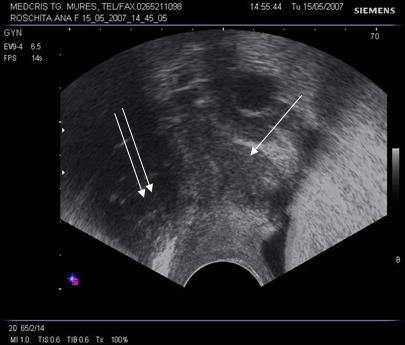

Fig. nr.391.

Endometriom ovarian vechi ,recidivat postoperator,

situat retrouterin

( sageata ). Se remarca ecogenitatea crescuta si asemanatoare ecostructurii endometriale uterine.